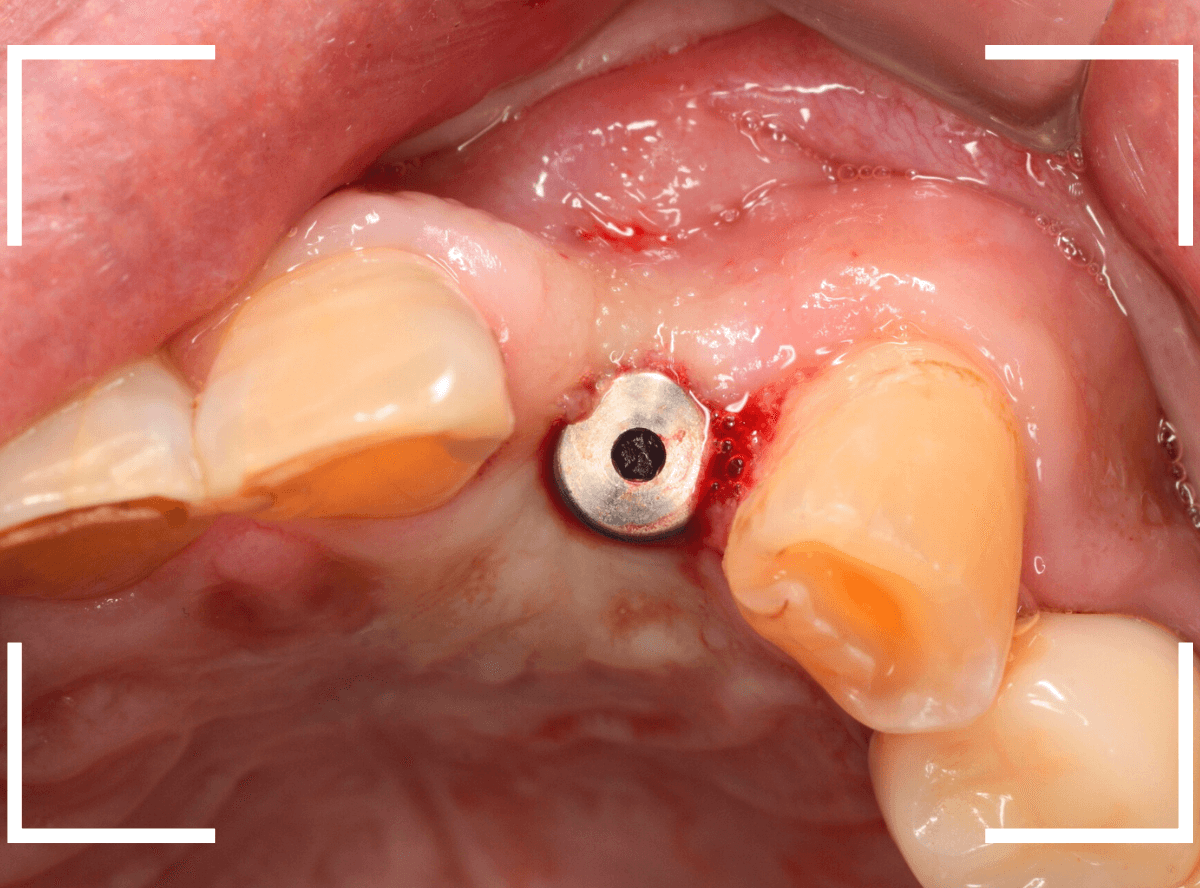

手術当日、インプラント体を埋入した直後です。

この状態で、しばらく経過観察をします。

インプラント体の周囲の骨と歯肉が落ち着くのを待って、型取りをします。